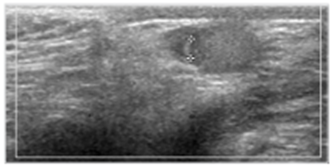

2) Epididymitis or Epididymo-orchitis: 사춘기 acute scrotum의 20% 정도를 차지. 사춘기 이전 소아의 1% 미만에서 발생. 이학적 검사상 epididymis가 커져 있으며 심한 압통을 호소하고 cremasteric reflex와 Prehn sign이 확인됨. Color doppler US 에서 epididymis내 혈류가 매우 증대된 소견이 보임.

testis 및 epididymis의 혈류가 매우 증가된 소견이 보인다.